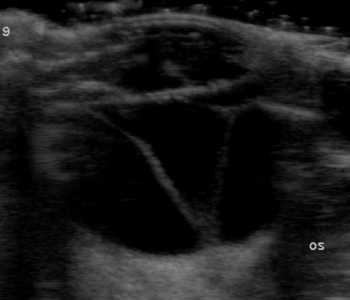

【網膜電位図(ERG)検査】

ERG検査とは、網膜に光を当てて刺激することにより発生する電気信号を計測して、光受容体の機能や網膜の細胞の活動を評価します。これにより、網膜に異常がないかを評価します。

網膜電位図

網膜電位図検査(ERG検査)